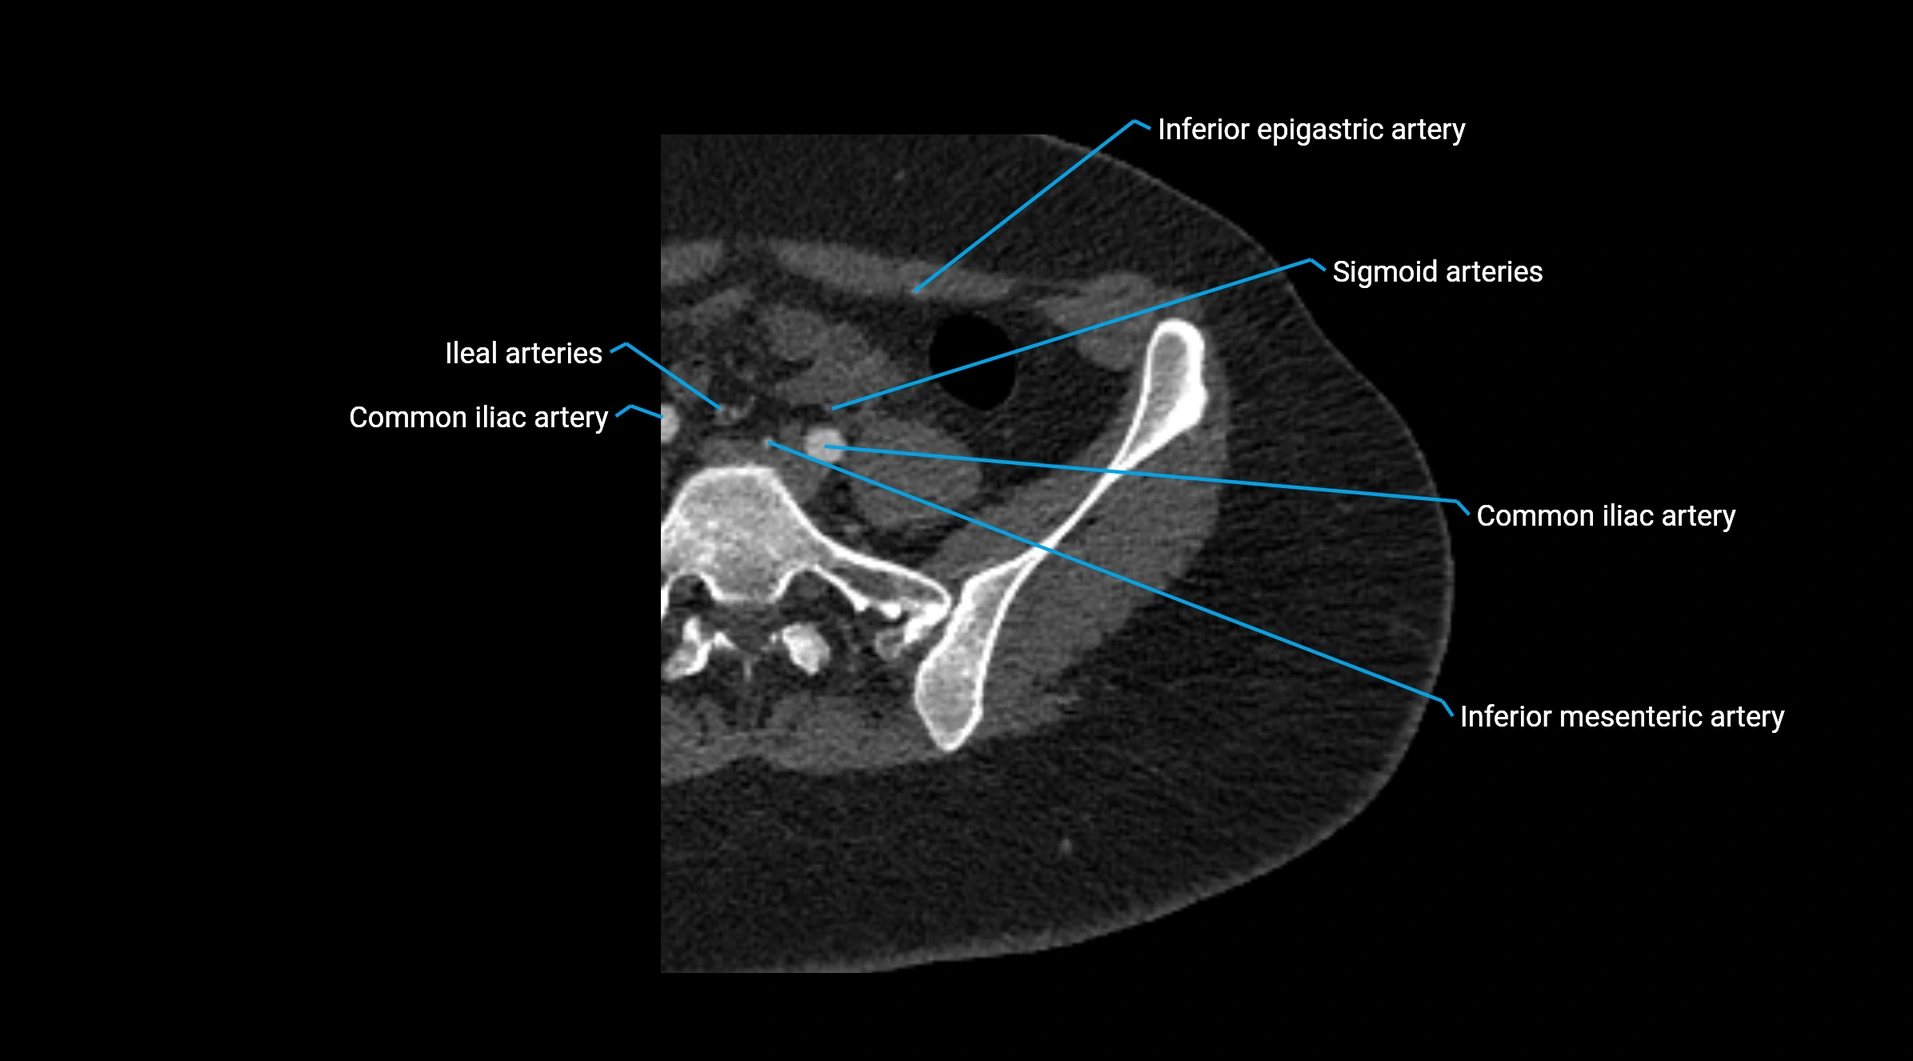

CT images

image

Contrast-enhanced CT (CTA):

• Gold standard for abdominal aortic imaging

• Provides excellent detail of lumen, wall, aneurysm, thrombus, and branch vessels

• Multiplanar and 3D reconstructions help in aneurysm measurement, stent graft planning, and dissection evaluation

• Unpaired visceral branches: celiac trunk, superior mesenteric artery (SMA), inferior mesenteric artery (IMA)

• Terminal branches: right and left common iliac arteries